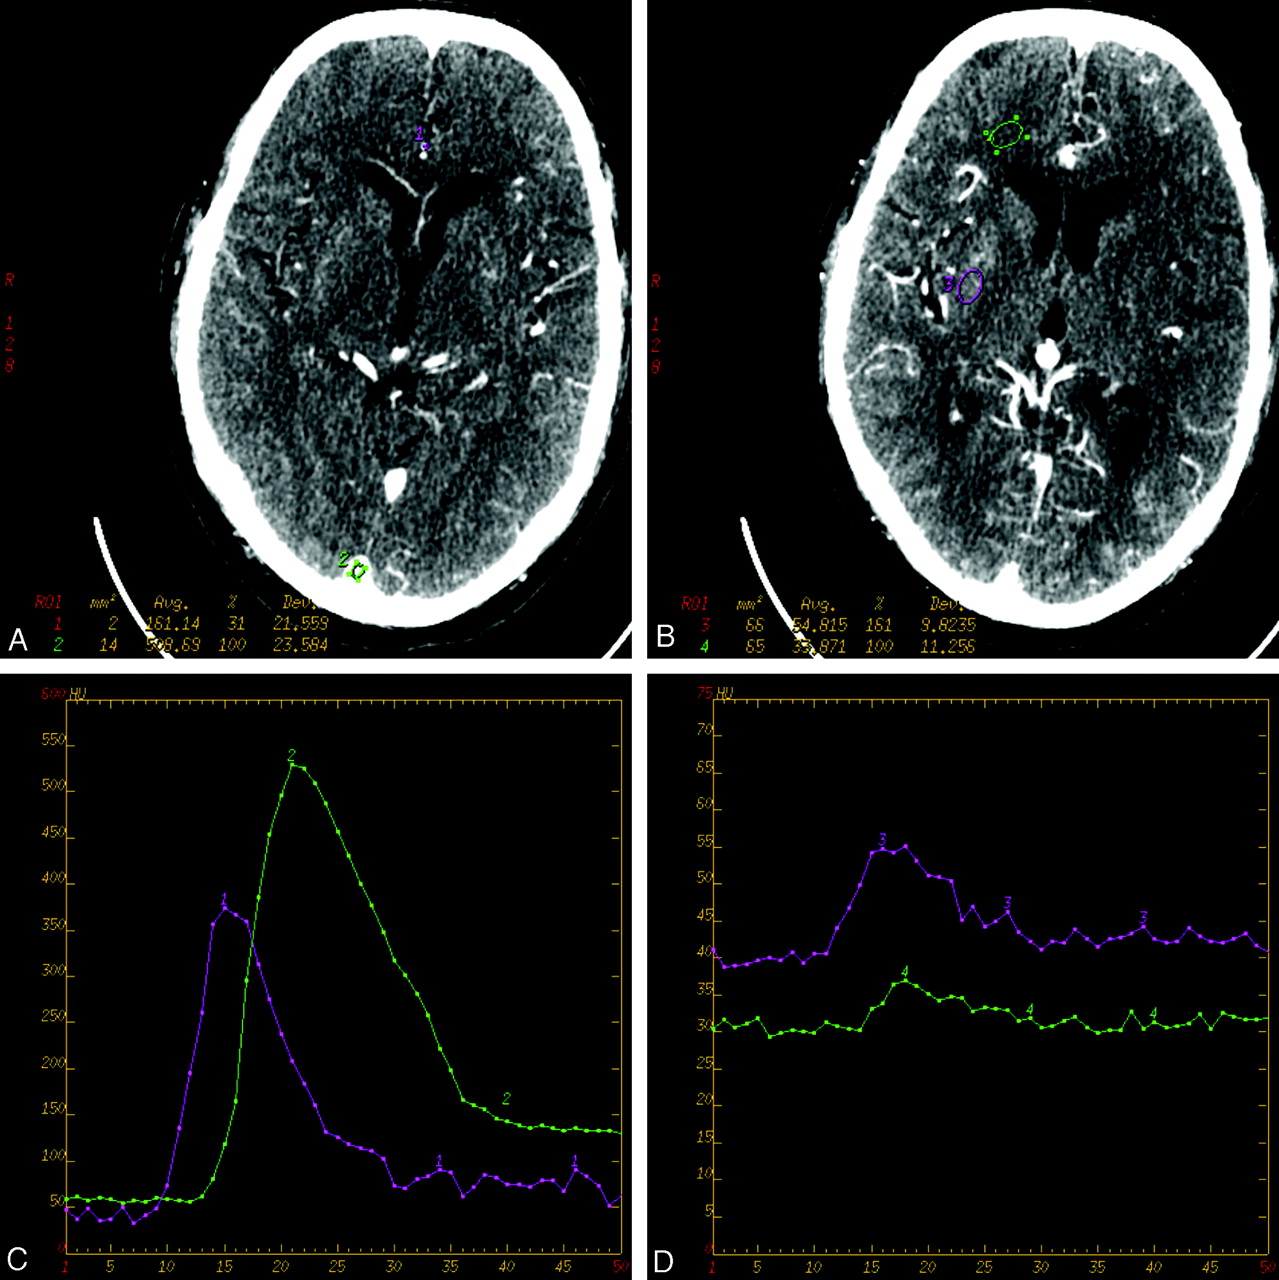

The increasing signal-intensity enhancement as a function of contrast concentration is presented graphically for each anatomic location in Fig 2. A linear increasing trend is clearly evident. The coefficients of correlation for each anatomic region were 0.98, 0.99, 1.0, and 0.95 for gray matter, white matter, artery, and vein, respectively.

Presented are the regression lines for each category of region of interest. There is a 25% increase in opacification for gray matter (A), 21% for white matter (B), 30% for the arterial input (C), and 12% for the venous output (D), between 300- and 400-mg/mL formulations of contrast agent.